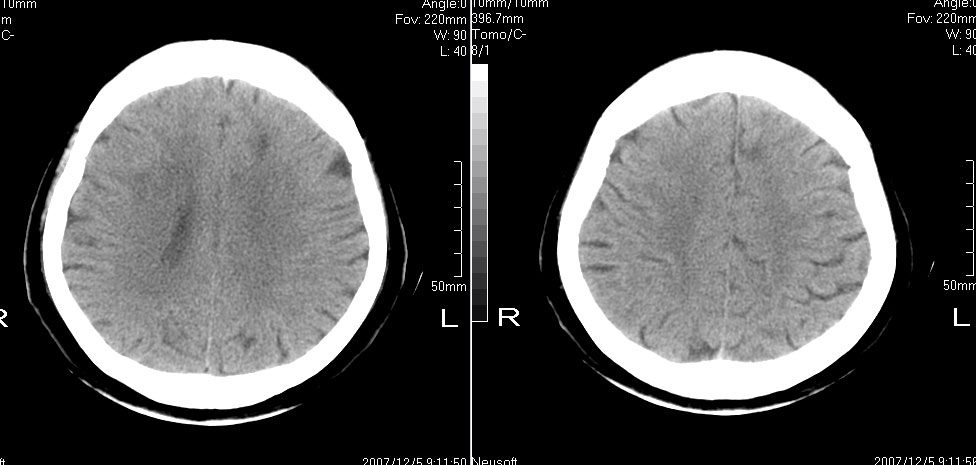

标题: CT10819:女,72,有高血压病史,突然寡言少语3日. [打印本页]

女,72,有高血压病史,突然寡言少语3日.

双侧基底节、左侧额叶 胼胝体膝部多发腔隙性脑梗塞。

双侧基底节、左侧额叶、胼胝体膝部多发腔隙性脑梗塞。支持!